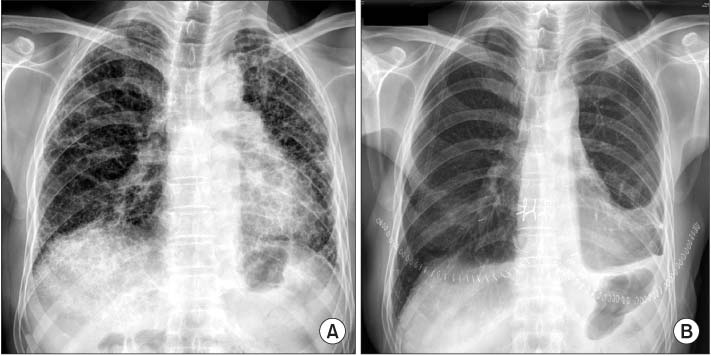

A bilateral double LT under sedation with remifentanyl was performed without any incidents. Seven days after LT, the patient developed nausea and became drowsy without focal neurologic signs. His blood pressure was 136/100 mmHg and pulse rate was 76 beats per minutes. Physical examination revealed no evidence of volume depletion or volume expansion. At the blood test, serum sodium was 129 mmol/L with a serum osmolality of 278 mOsm/kg and a urine osmolality of 493 mOsm/kg. His thyroid function was normal. Adrenocorticotropic hormone (ACTH) level was below 1.0 pg/mL (normal range, 7.3 to 63.3 pg/mL) and a rapid ACTH test showed adrenal failures with cortisol 0.6 µg/dL (normal range, 6.7 to 22.6 µg/dL) at baseline, 3.6 µg/dL at 30 minutes and 2.9 µg/dL at 60 minutes. Since corticosteroid supplementation for immunosuppresion after LT was considered as the cause of hypothalamic-pituitary-adrenal axis suppression and had maintained continuously, it was not likely that adrenal insufficiency was a cause of hyponatremia. A chest X-ray and chest computed tomography were normal except for postoperative changes (

Fig. 1Chest X-ray taken before lung transplantation (LT) (A) and 7 days after LT (B). Chest X-ray shows no signs of pulmonary edema except for postoperative changes.